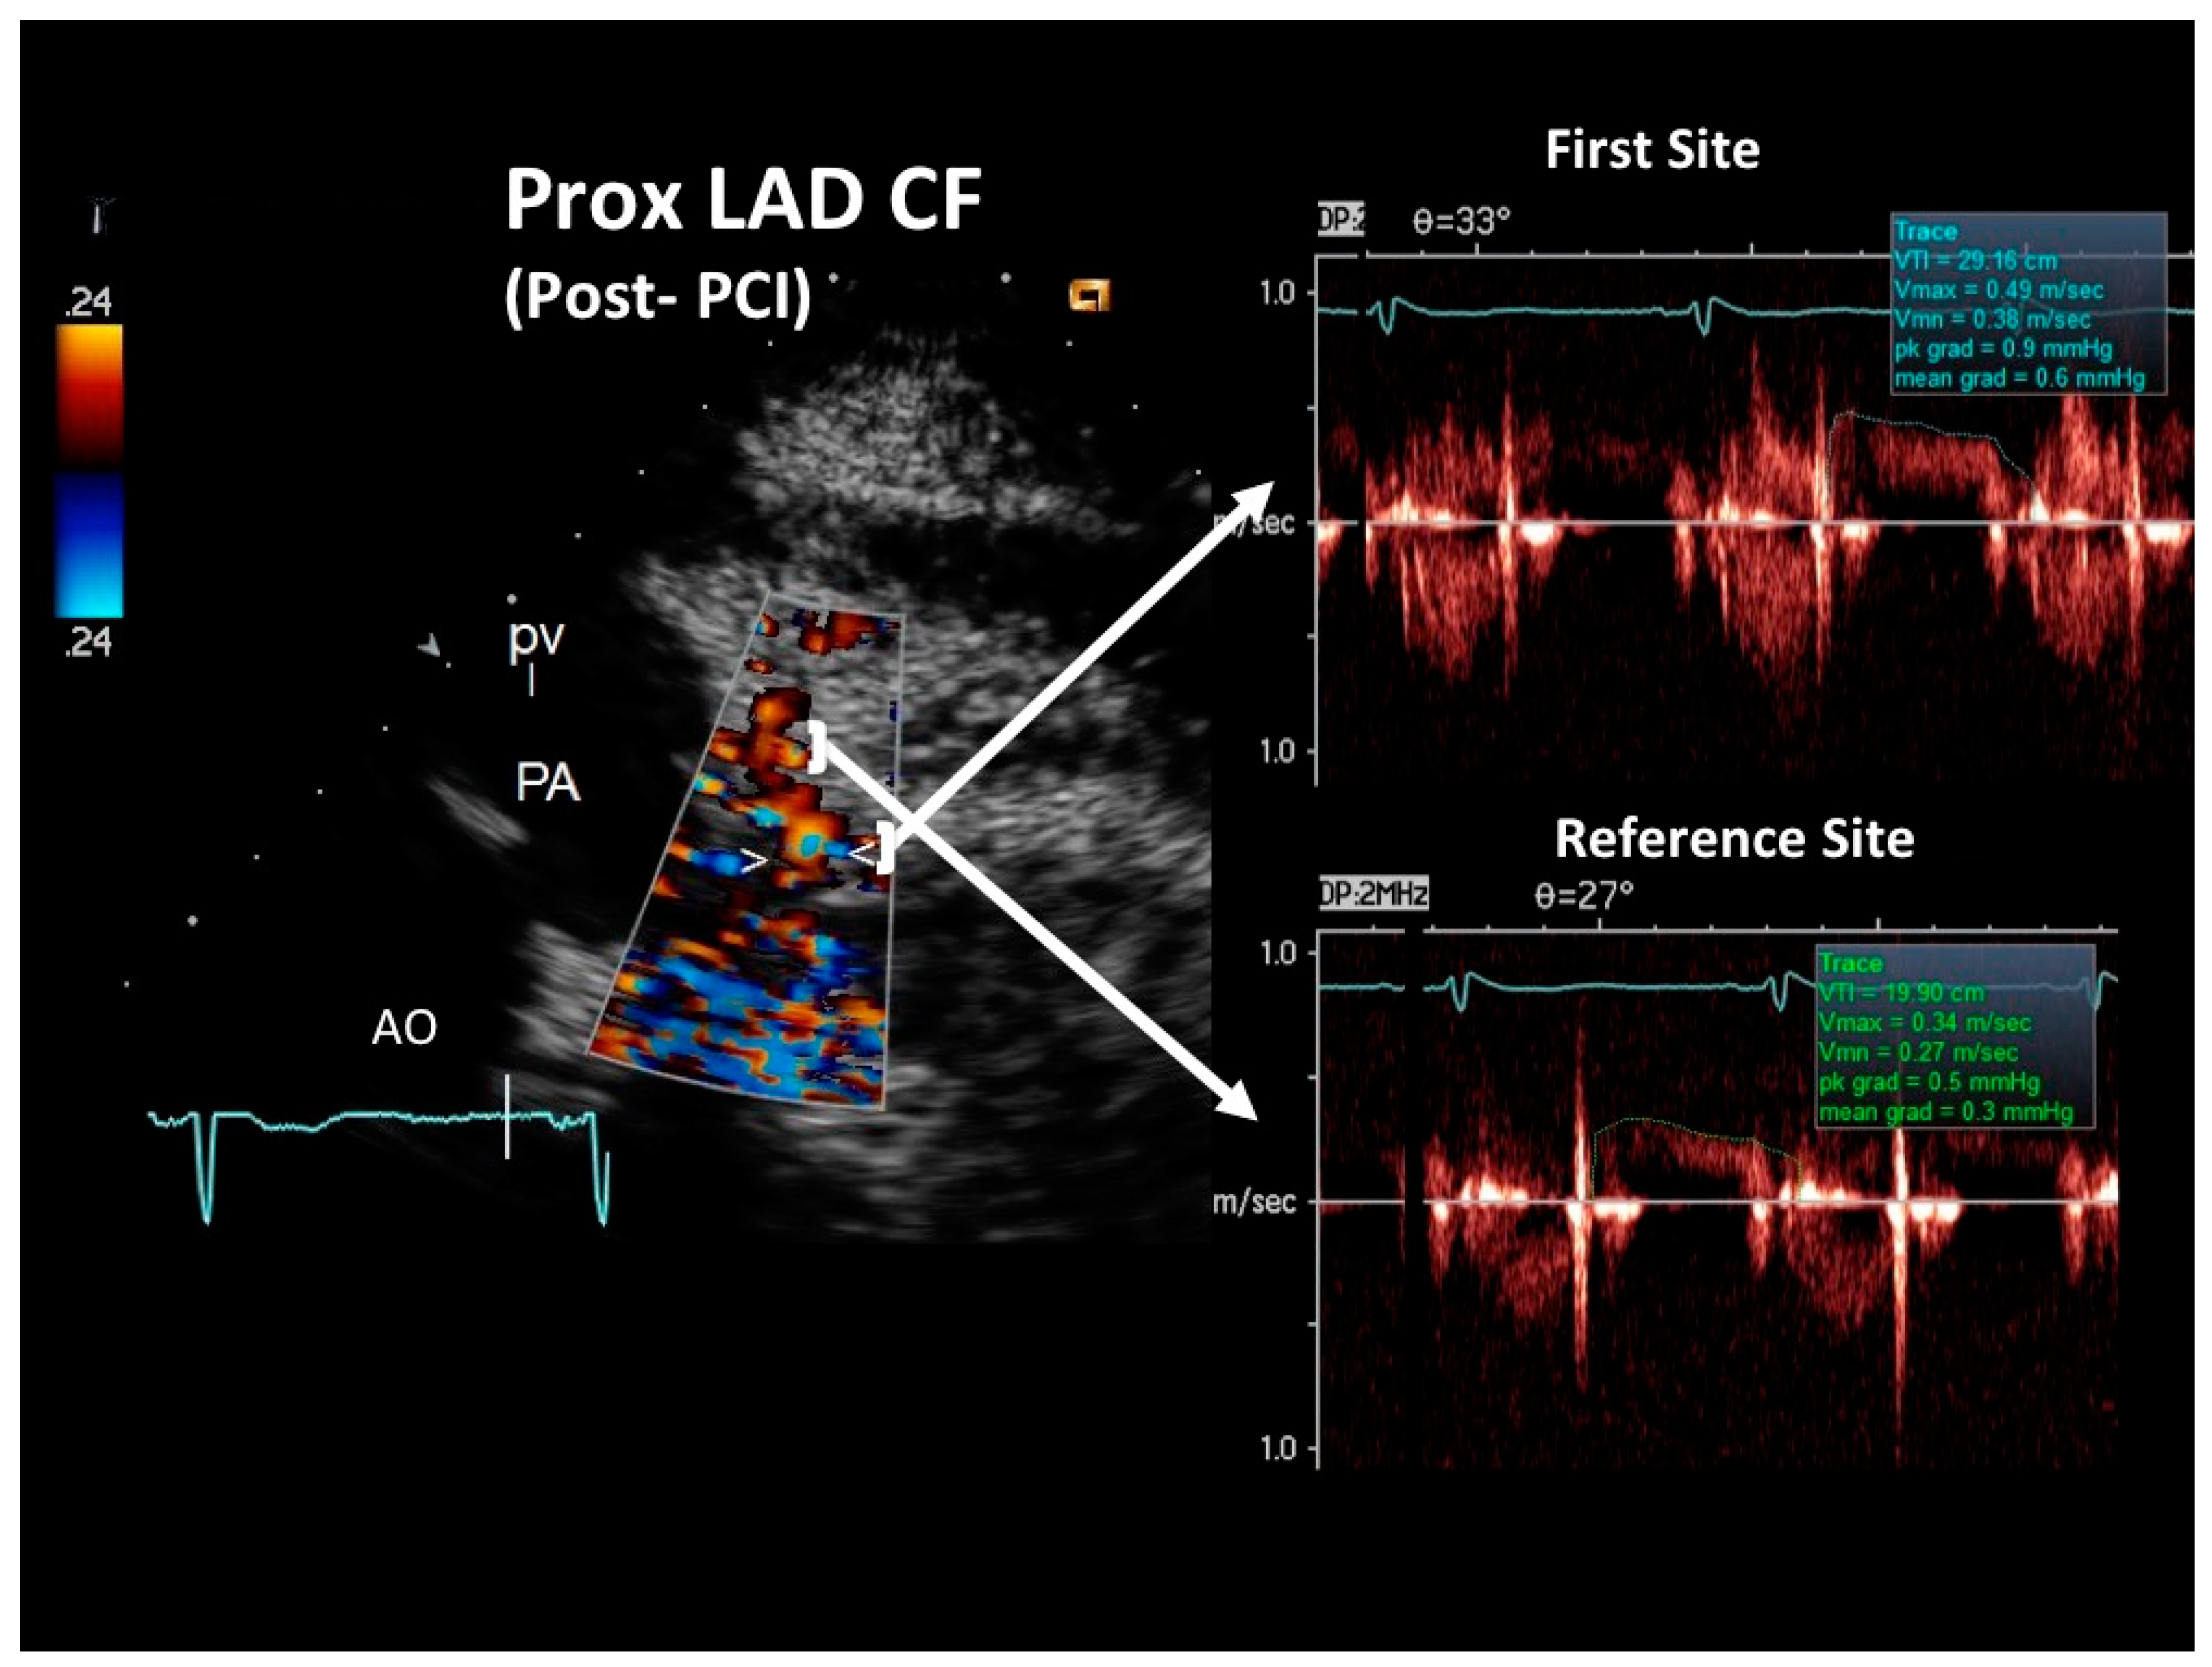

Figure 5. Blood flow Doppler recording by E-Doppler TTE in the proximal LAD after stenting in the follow-up (same format as in the acute phase). Maximal velocity had dropped to 49 cm/s, yielding a residual stenosis area of 25% according to the continuity equation. The diastolic waves of the Doppler tracings are outlined in green, and the maximal velocity and time velocity integral are reported. Abbreviations as in Figure 2.

At the COVID intensive care unit, he was admitted to the catheterization laboratory, where he received immediate intravenous therapy, 5000 IU heparin sodium, 250 mg lysine acetylsalicylate and cangrelor bolus followed by continuous infusion (according to body weight). Coronary angiography showed sub-occlusive stenosis (lumen narrowing = 86%) of the proximal LAD (Figure 4), which was treated with balloon angioplasty followed by drug-eluting stent placement (Resolute Onyx 2.75 × 34 mm). Following the intervention, 0% residual stenosis was recorded, with an optimal residual flow and no dissection present (Figure 4). A total of 2 hours post-procedure, 180 mg oral ticagrelor (after the suspension of cangrelor) was administered, followed, from the following day, by 100 mg oral aspirin daily, 90 mg oral ticagrelor bis in die (as part of a dual antiplatelet regimen) and goal-directed medical therapy with a beta-blocker and highly intense statin therapy [19]. The ECG following PCI displayed persistent pseudo-normalization of T waves in the precordial leads; cardiac high-sensitivity troponin T (III assay) increased considerably to 3734 μg/L. Patient recovery was event-free, and he was transferred on the fourth day to the internal medicine department, pending the negativization of the SARS-CoV-2 molecular assay. He was discharged on the 7th day on dual antiplatelet therapy but not on anticoagulation therapy since his COVID infection had no thromboembolic complications [20]. After two months, he was re-evaluated by E-Doppler TTE, this time adding CFR assessment. The transtenotic velocity had dropped almost completely, indicating a patent stent (minimal residual stenosis at 26% of area reduction according to the continuity equation) (Figure 5), and the CFR was also normal (=3.3) (Figure 6), confirming the stent patency and complete recovery of microcirculatory function in the LAD myocardial territory.

As expected, the reference distal flow velocity was low (Figure 2) and mildly increased after PCI (Figure 5). A long severe stenosis can reduce basal flow and flow velocity distally to the obstruction. This, however, does not hamper stenosis severity assessment by the continuity equation as previously demonstrated. Even if the stenosis is very severe (>85% diameter narrowing) and there is a reduction at rest of the flow distally to the stenosis, as demonstrated by the landmark Gould study [36], the flow at the stenosis and in the post-pre-stenotic segments must be the same. This arises on the basis of the principle of continuity of flow, which is a corollary of the law of conservation of mass, which states that the flow in any portion of a non-branching tube is equal: what comes in must come out [25]. Problems can arise in cases of collaterals between the stenosis and the sampling site, since flow could be diverged to the collaterals and so create flow differences between the sampling site and the stenosis, causing inaccurate estimation of the % lumen narrowing with the continuity equation [37,38]. However, as demonstrated in a recent in vitro study [38], since there is a certain pressure drop in the post-stenotic segment, such a divergent flow to collaterals is much less important in cases of sampling distally to the stenosis than proximally, owing to a reduced driving pressure toward collaterals in the distal compared to the proximal segments. Therefore, the authors of that paper suggest that as a general rule, it is better to sample the reference distally (as in our case) rather than proximally, owing to the risk of such collaterals.

The good reproducibility of the method, as recently reported, allows a reliable follow-up of the transtenotic velocity [13]. In fact, the repeatability coefficient of % CSA (cross-sectional area) stenosis is 13.8% (95% CI: 10–22%), meaning that a % CSA stenosis variation exceeding this value is a real variation and not a random noise of the technique. In our case, when assessing by E-Doppler TTE, the variation of % CSA was much larger than the repeatability coefficient of % CSA (from 89% to 25% of CSA), pointing out the effective reduction of the stenosis by the PCI procedure, as confirmed by post-PCI coronary angiography. The residual intra-stent acceleration contrasting the absence of stenosis by angiography is a frequent finding, as already pointed out using the intravascular Doppler flow wire technique [39] and confirmed by our method [12].